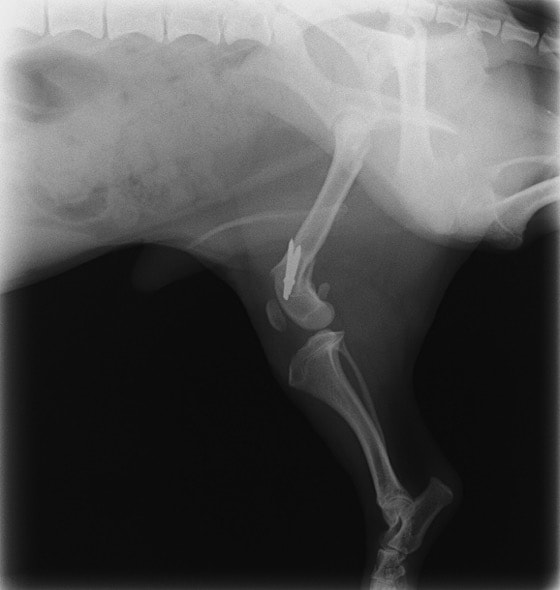

症例:交通事故による椎体脱臼

柴犬:9歳、避妊雌

交通事故直後、胸腰部に激しい疼痛、両後肢に完全麻痺を認め、シェフシェリントン徴候を呈していました。レントゲン検査において、第11-12胸椎間の脱臼が認められました。

脊髄の減圧、脊柱管の再構築・安定化を目的に、片側椎弓切除術およびMatrixMANDIBLE Plateによる椎体固定を実施しました。

隣接椎体を架橋するようにプレートを設置しました。

術後レントゲン写真